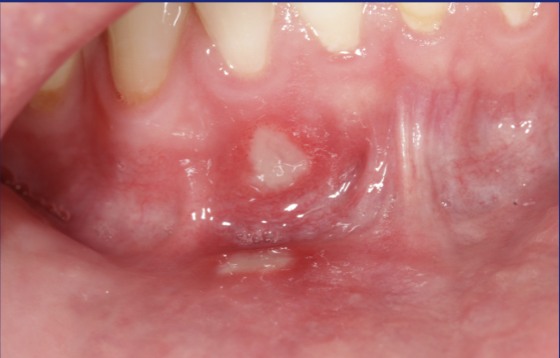

Pyogenes granuloma

What this is?

Appears on the gingival margins, ulcerated appearance and is thought to be an over response to irritation - usually excised - what am i ?